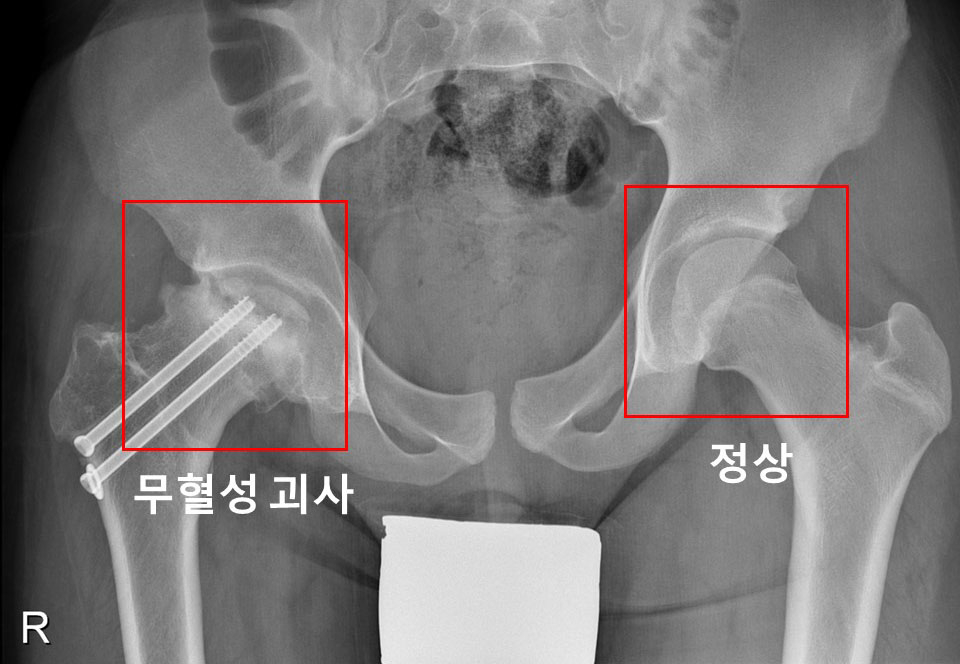

허벅지뼈(대퇴골) 위쪽의 성장판 부위에서 대퇴골두와 그 아래 뼈가 특별한 외상이 없는 데도 분리될 때 대퇴골두 골단 분리증으로 진단한다. 진단이 늦어지면 대퇴비구 충돌증후군, 대퇴골두가 썩는 대퇴골두 무혈성 괴사가 발생할 수 있다.

또 연구팀은 △갑상선 기능 저하증 △중추성 성조숙증 △뇌하수체 기능 저하증 △성선 기능 저하증 △성장호르몬 결핍증 △부갑상선 기능 항진증 △선천성 부신 생식기 장애 △거대증 △가성 부갑상선 기능 저하증 등 각 내분비질환 별 대퇴골두 골단 분리증의 발병 위험을 분석했다. 그랬더니 성장호르몬 결핍증으로 성장호르몬 치료를 받는 환자군에서 대퇴골두 골단 분리증의 발병률이 일반인보다 약 65배로 가장 높은 것으로 나타났다.